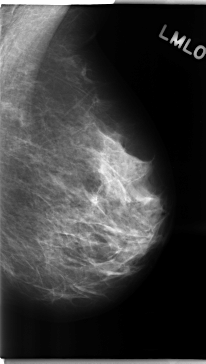

C_0194_1.LEFT_MLO

LEFT_MLO LINES 4720 PIXELS_PER_LINE 2672 BITS_PER_PIXEL 12 RESOLUTION 50 NON_OVERLAY